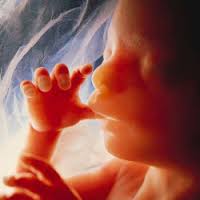

LA ECOGRAFIA ha marcado un antes y un después en el control del embarazo. Es la prueba prenatal más importante por la cantidad de información que es capaz de ofrecer. Gracias a las ecografías en el embarazo se puede evaluar el desarrollo intrauterino del bebé, por lo que es vital desde el punto de vista médico, pero también permite a los padres ver a su hijo y oír sus latidos antes de nacer, siendo también muy valiosa en el plano emocional.

También es conocida como ultrasonografía o eco sonografia y consiste en una técnica no invasiva que permite, a través de ondas de ultrasonido, ver imágenes de órganos y estructuras dentro del cuerpo, y en el caso de las embarazadas, examinar el feto dentro del útero materno.

La ecografía en el embarazo es utilizada principalmente para estudiar el crecimiento y bienestar del bebé dentro del útero. Permite, entre otras cosas, detectar malformaciones, evaluar el desarrollo anatómico del feto, su crecimiento, su posición, calcular su edad gestacional, oír sus latidos, observar el estado de la placenta, del líquido amniótico, estimar el peso del bebé y detectar anomalías o patologías del embarazo.